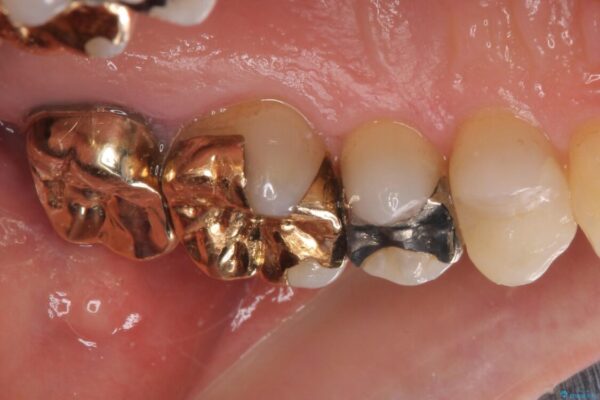

奥歯の銀歯が外れてしまったため、セラミック治療を希望された患者様です。

治療前

• 外れてしまった銀歯 セラミックインレーで自然な仕上がりに 治療前画像